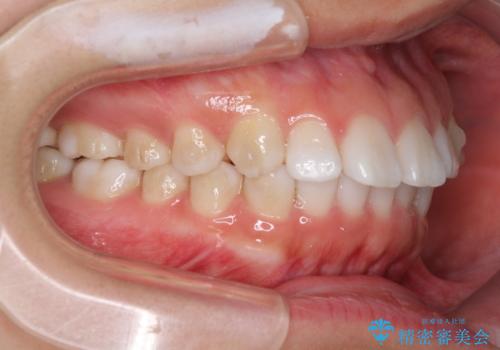

インビザラインによる軽度な出っ歯の矯正治療

- 上の前歯の出っ歯を治したいとのことで来院された患者様です。

上下顎ともにIPR(歯と歯の間を削る)と歯列全体の拡大によって口元が引っ込むように設計し、インビザラインにより治療を行うこととしました。

どこまで口元を引っ込めることができるのか、患者様自身も正直分からない部分があったため、少しずつ治療ゴールを変更しながら仕上げていきました。

気になっていた前歯の飛び出した印象は、最終的にはスッキリと引っ込み、大変満足していただきました。